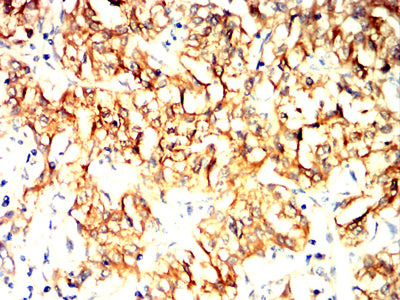

分类: 科研抗体货号: 32405别名: 42A; 18A2; CAPL; FSP1; MTS1; P9KA; PEL98应用: IHC,FCM反应种属: Human, Mouse, Rat